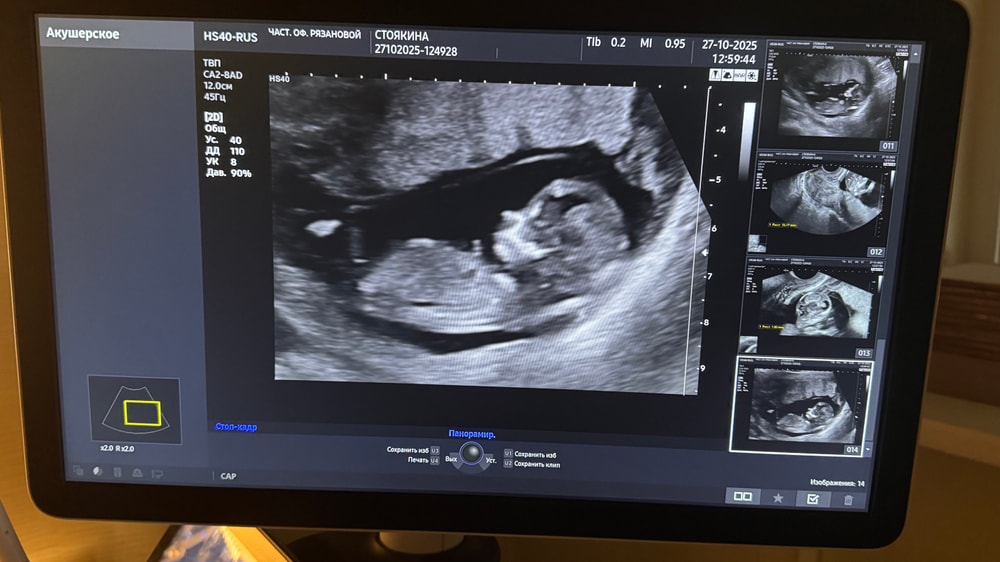

Первый скрининг пройден

Анализы, скринингиКтр67мм

Твп 2.2 мм

Сб167 уд